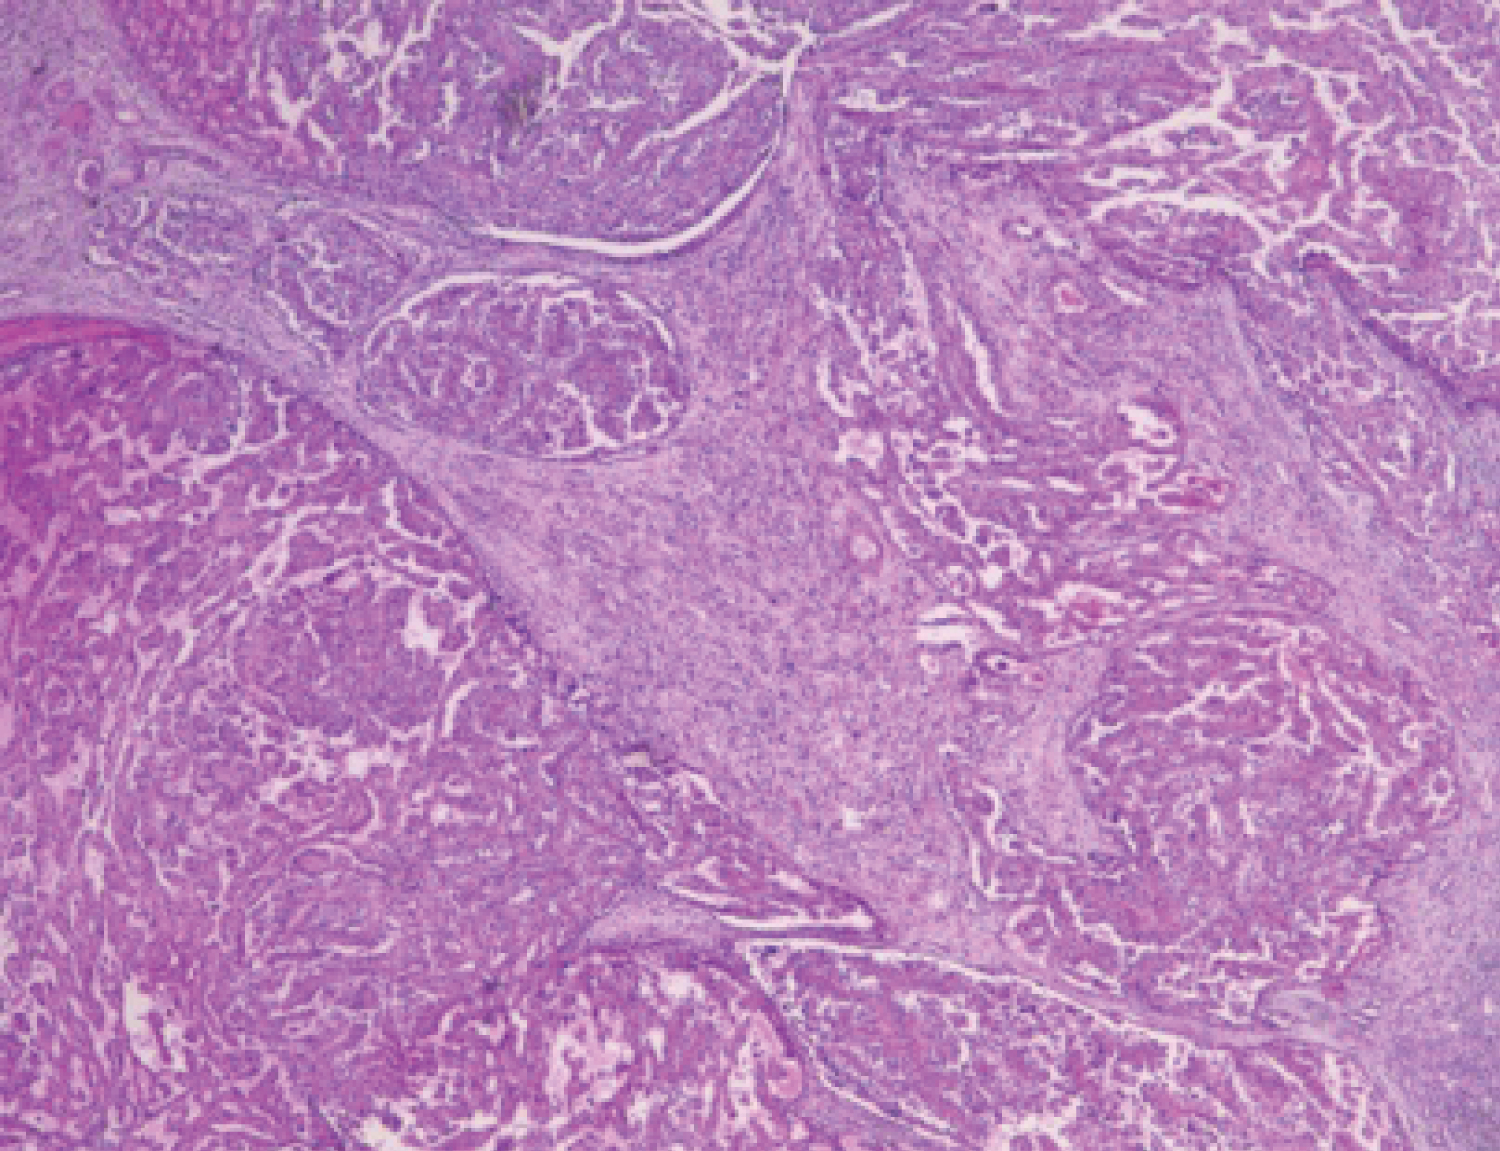

Clinically, patients with Xp11.2 translocation RCC are typically admitted to the hospital because of hematuresis, abdominal pain, or an abdominal mass, and the presence of occupying lesions is confirmed using radiography, kidney color doppler ultrasonography, and CT. As this presentation is similar to that of common adult RCC subtypes such as conventional clear cell RCC and papillary RCC (PRCC), the frequency of Xp11.2 translocation RCCs in adults may be underestimated. One single-institution study subjected 433 adult patients to cytogenetics and TFE3 immunohistochemical analyses and found that Xp11.2 translocation RCCs accounted for 1.6% of the cases [10]. With that in view Xp11.2 translocation RCC should be considered when tumors exhibit a suspicious pattern [11]. But as shown by a systematic review and meta-analysis of observational studies, no significant differences were observed in the prognosis between children and adults, and between female and male [12] (Figure 1 and Figure 2).

Figure 1: Microscopic appearance of renal cell carcinoma (RCC) with typical papillary architecture.

Figure 2: Microscopic appearance of renal cell carcinoma (RCC) with typical papillary architecture.